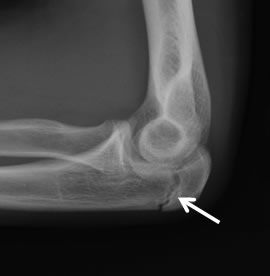

Posterior elbow impingement, also known as postero-medial olecranon impingement (PMOI) is the most common type of injury associated with throwing-induced elbow injuries (1). PMOI is caused by excessive and repetitive valgus stress (1,2). This repetitive valgus stress various changes within the articular surface of the olecranon and ulna such as osteophyte formation and loss of joint space (1,2). The forces applied to the elbow when following through with the throw can cause osteochondral changes that lead to having a symptomatic posterior elbow (2).

CT imaging has been proven to be gold-standard for the assessment of the elbow with a throwing history (1). CT has been shown to identify joint space narrowing and medial olecranon subluxation related to PMOI (1).